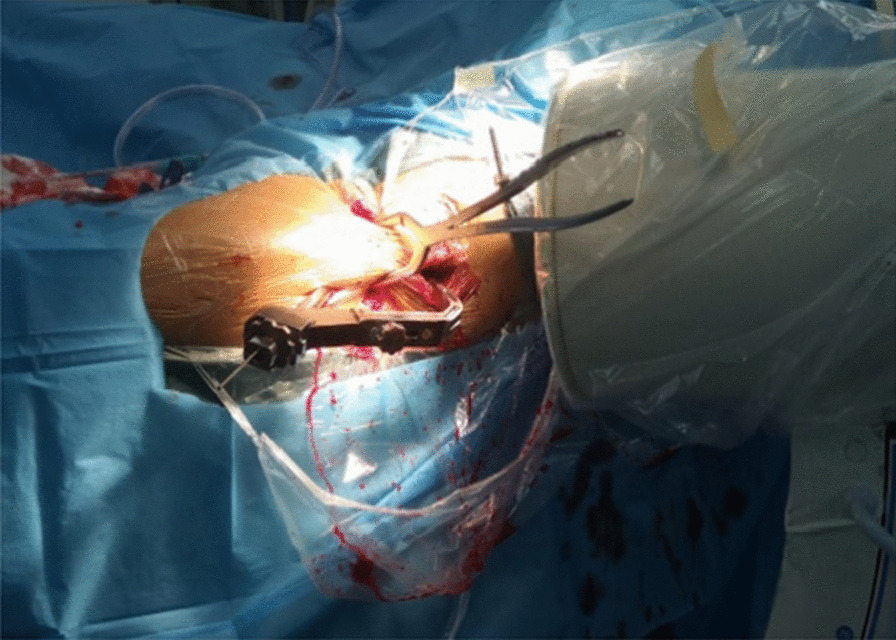

Fig. 1.

First, the femoral artery, femoral vein and femoral nerve are located in the inguinal area, and then a minimally invasive reduction incision is made approximately 2–3 cm below the inguinal area (femoral intertrochanteric line area)

Fig. 2.

The reduction clamp with minimally invasive clamp reduction of the anterior approach does not interfere with the intramedullary nail implantation device